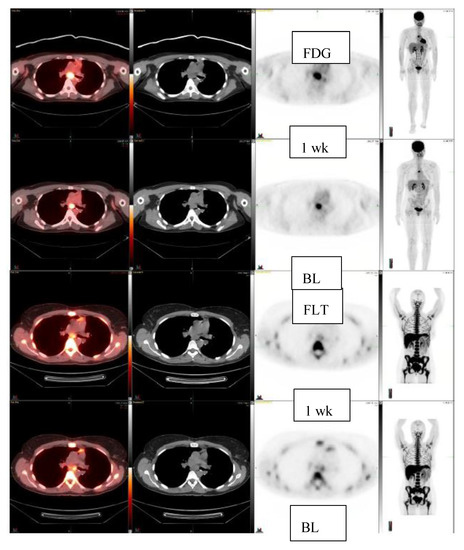

| 42/F | Clear cell sarcoma, Left foot Subcarinal lnn | 3.0 2.2 × 1.2 | 2.6 2.3 × 1.5 1 week | −13% | |

| 39/M | High grade sarcoma, RLL mass | 7.2 4.8 × 2.7 | 7.5 4.8 × 2.6 1 week | +4% | |